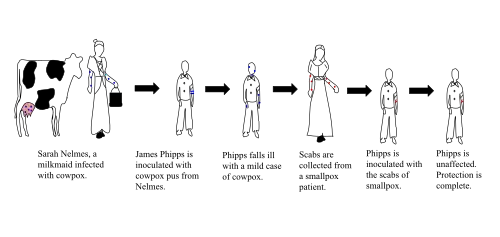

Jenner postulated that the pus in blisters from sufferers of cowpox (a disease similar to smallpox but much less virulent) protected them from smallpox. On 14 May 1796, Jenner tested his hypothesis by inoculating James Phipps, the eight-year-old son of Jenner's gardener. He scraped pus from cowpox blisters on the hands of Sarah Nelmes, a milkmaid who had caught cowpox from a cow called Blossom[35] (whose hide now hangs on the wall of the St. George's Medical School library, now in Tooting, London). Phipps was the 17th case described in Jenner's first paper on vaccination.[36]

Jenner inoculated Phipps in both arms that day; this led to a fever and some uneasiness but no full-blown infection. Later, Jenner injected Phipps with variolous material, the routine method of immunization at that time and again no disease followed. The boy was later challenged with variolous material and again showed no sign of infection. There were no unexpected side effects, and neither Phipps nor any other recipients underwent any future 'breakthrough' cases.

US physician Donald Hopkins has written, "Jenner's unique contribution was not that he inoculated a few persons with cowpox, but that he then proved [by subsequent challenges] that they were immune to smallpox. Moreover, he demonstrated that the protective cowpox pus could be effectively inoculated from person to person, not just directly from cattle."[39] Jenner successfully tested his hypothesis on 23 additional subjects.